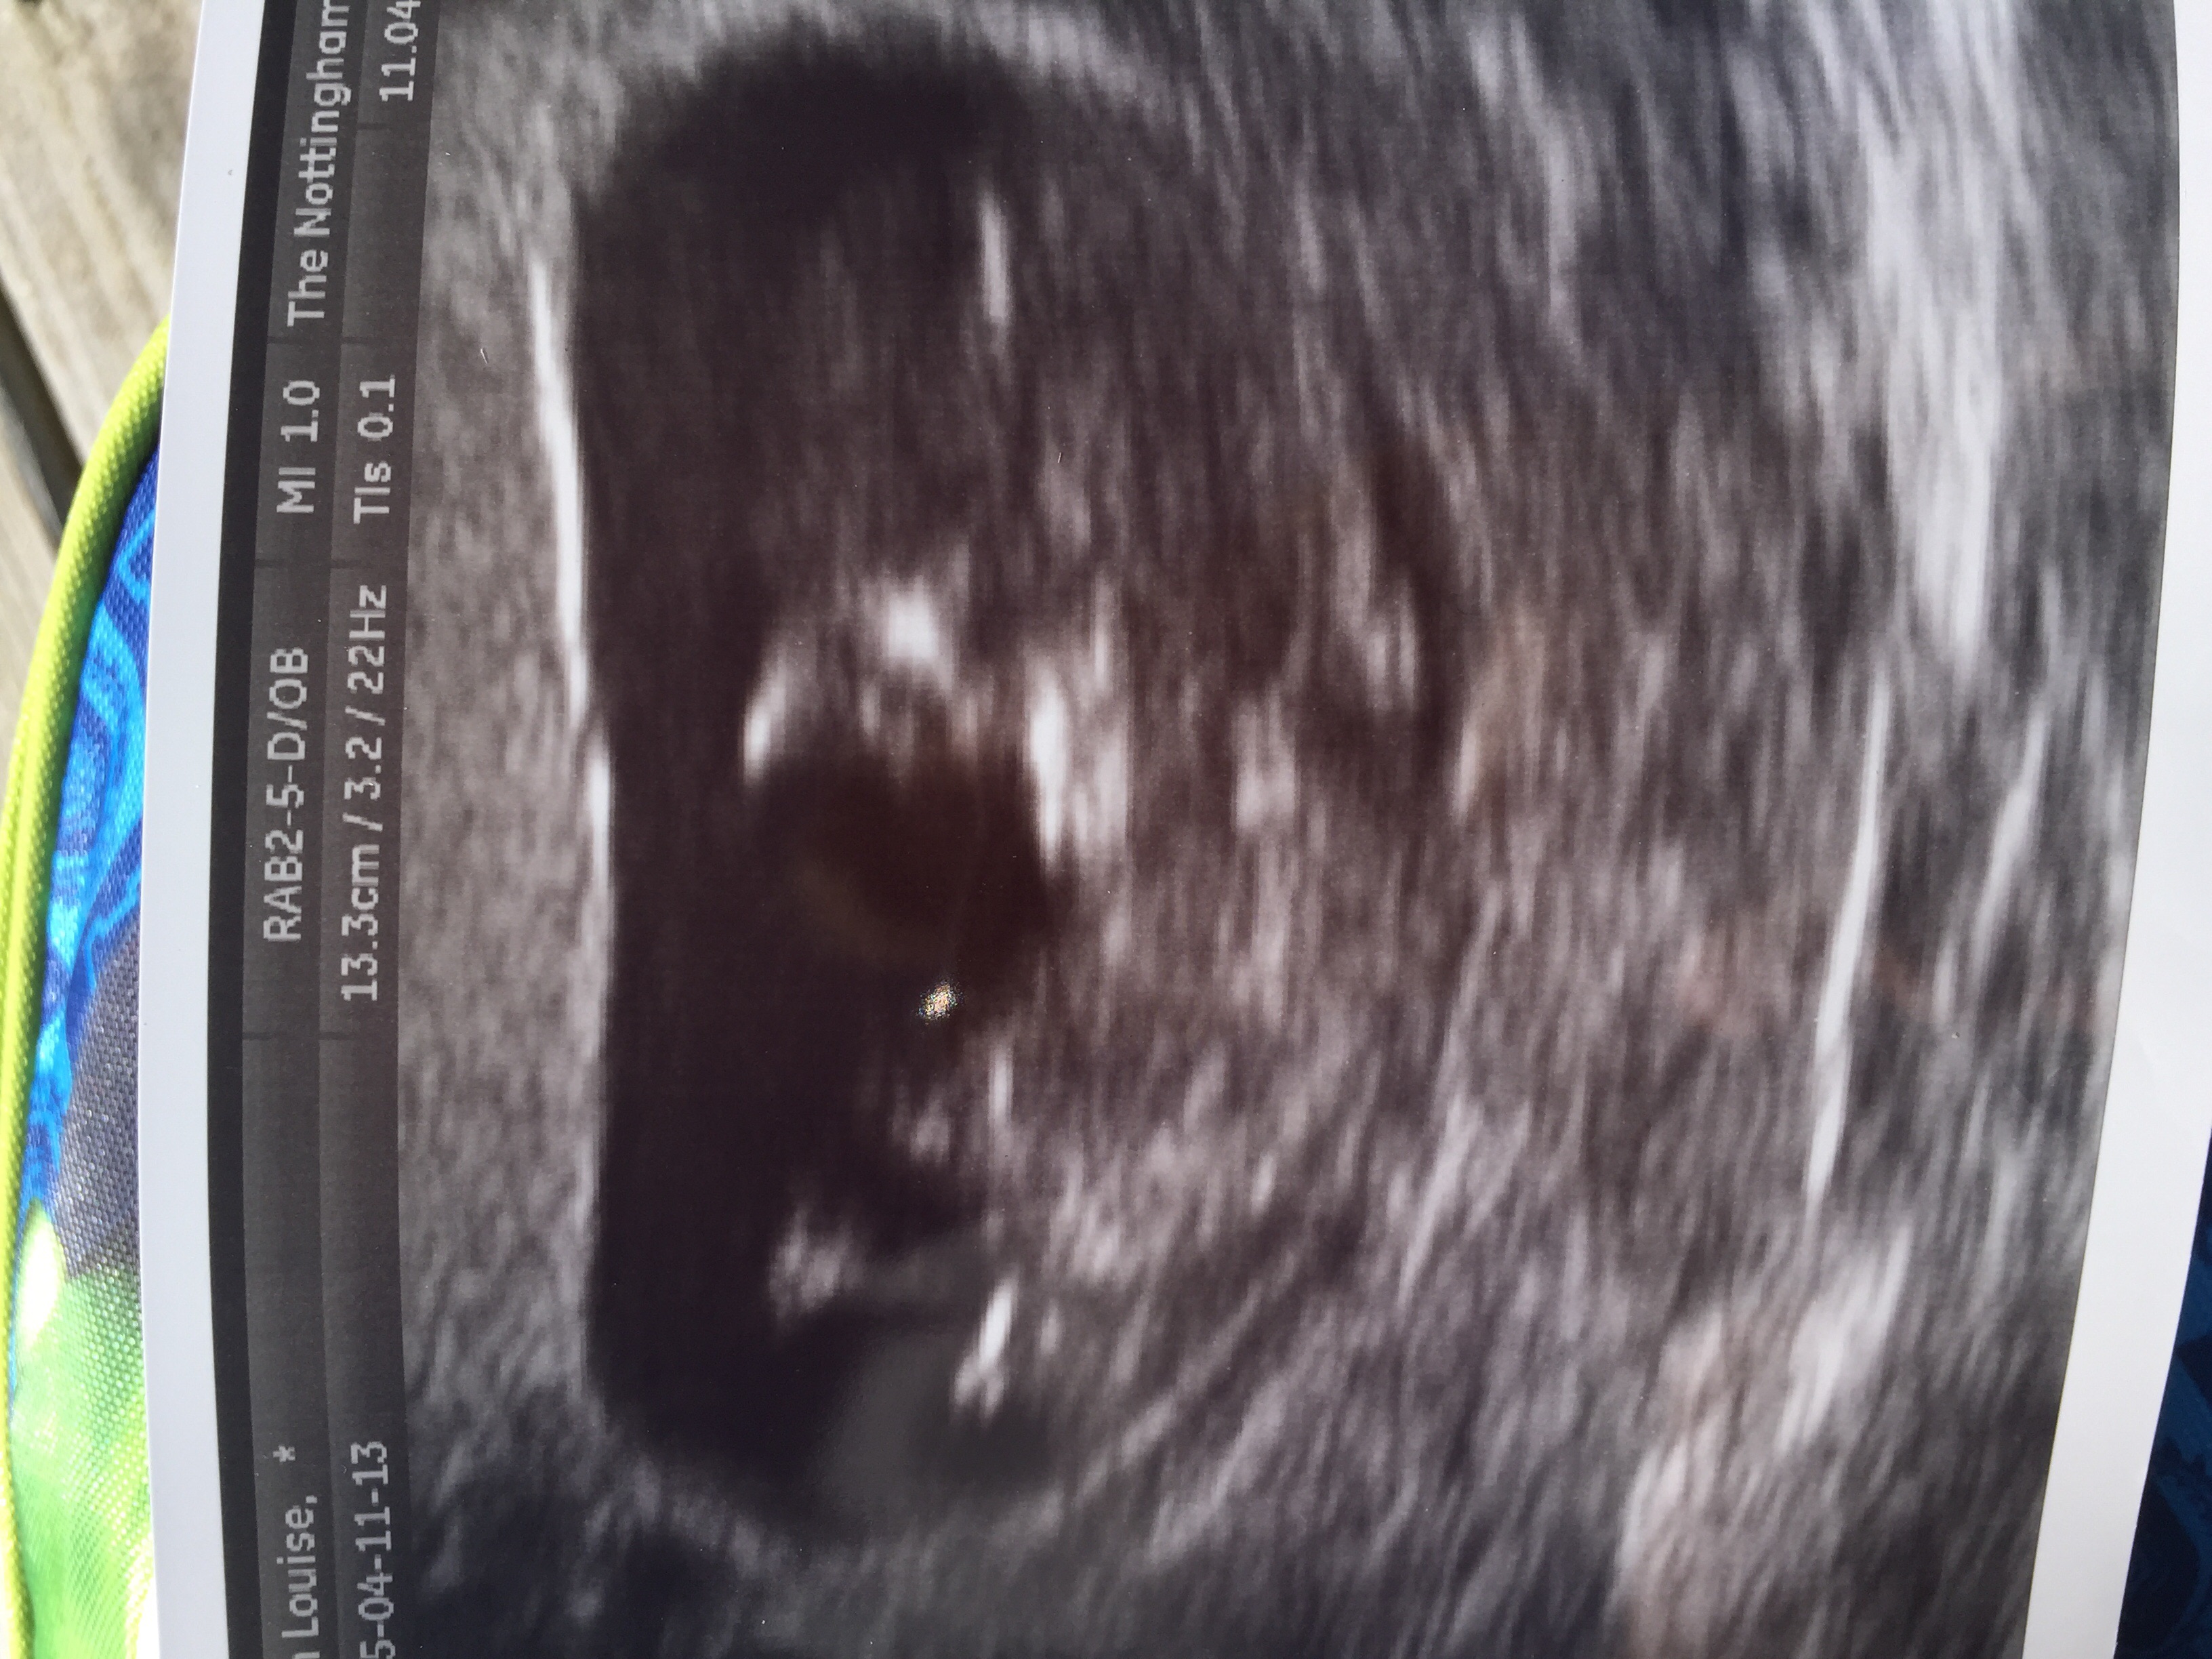

So, I've had a private 11 week scan today. The tech said it was too early to say but she had a fair guess as the nub was "so clear"

Can I ask for opinions on the nub?

Is that a boy nub?

I would of thought girl as it's forked? X

Sorry, now I see it! Yes, girly flat forked nub! I was looking at the cord at first.

Girl - Too early to tell but if this was 12+ weeks I'd say girl x

The tech was insistent it is a girl.